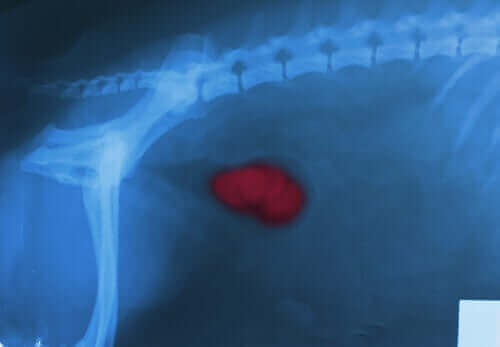

Neoplasi

Neoplasier, hvad enten de er godartede eller ondartede, er unormal og overdreven vækst af væv i specifikke dele af kroppen. For eksempel forårsager prostatahyperplasi, hæmangioma eller hæmangiosarkom ofte blødning.